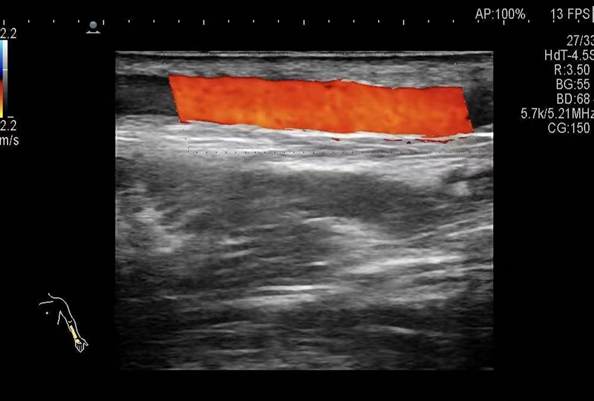

▲术后,血管开通,血流恢复